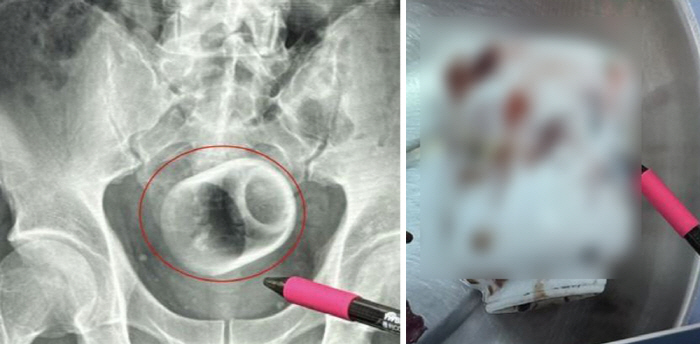

의료진은 X-레이 검사에서 지름 6cm, 높이 8cm의 도자기 컵이 남성의 항문 내부에 자리 잡고 있는 것을 발견했다. 처음에는 의료 기구를 이용해 제거를 시도했지만 표면이 매끄러워 실패했다. 결국 복부 절개 수술을 통해 안전하게 꺼냈다.